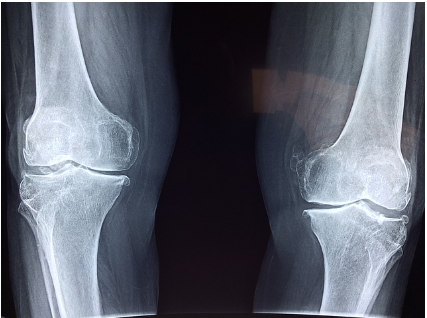

2. X-레이: 뼈의 상태를 확인할 수 있는 기본적인 영상 진단 방법입니다. 골절, 관절염, 뼈의 변형 등을 확인할 수 있습니다.